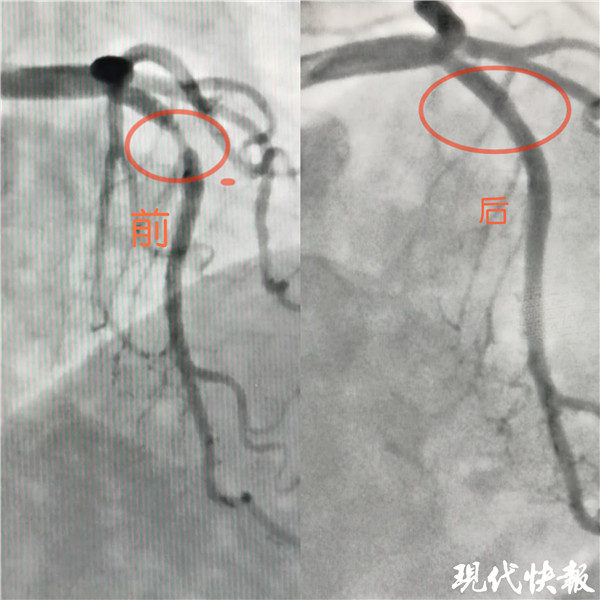

記者了解到,入院后完善冠狀動(dòng)脈造影檢查示,張女士LM正常,LAD近段血管90%狹窄, LCX及RCA未見(jiàn)狹窄?;窗彩幸辉盒膬?nèi)科介入治療團(tuán)隊(duì)嚴(yán)格把握適應(yīng)癥,和患者及家屬溝通后,于LAD病變處植入一枚藥物可吸收支架,術(shù)后血管內(nèi)超聲檢查提示支架貼壁良好。